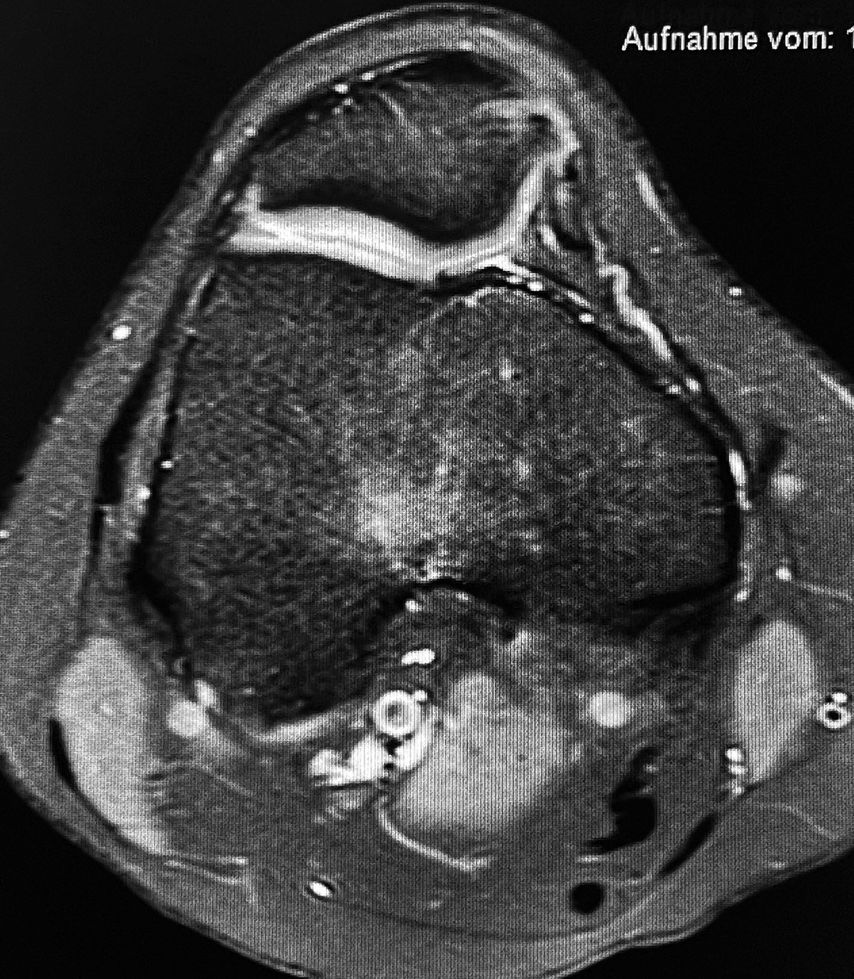

13-jährige Patientin, Zustand nach MPFL-Plastik

4 Jahre nach der Operation stürzte die Patientin neuerlich auf das Kniegelenk, was eine Reruptur der MPFL-Plastik zur Folge hatte (Abb. 1). Die Revisions-MPFL-Plastik erfolgte mit der Quadrizepssehne.